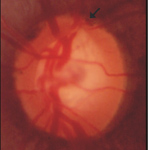

青光眼造成的傷害是無法回復的,如何減少青光眼的傷害是一個重要的課題,「早期發現、早期治療」是對付青光眼的主要策略。由於大部份的青光眼是沒有症狀的,所以「定期追蹤檢查」是發現青光眼的重要方法,四十歲以上的成人應至少每年作一次篩檢,有前述危險因子者更應至少每半年作一次篩檢。檢查的項目包括眼壓及視神經(眼底)(如:圖二),檢查結果異常者, 要進一步作視野檢查(如:圖三)。視神經盤的檢查是目前已知最可靠診斷出青光眼的方法,可藉由眼底鏡來檢查視神經盤與視神經纖維層,惟必須有足夠的經驗才能判定結果。傳統的視野檢查雖然無法早期診斷出青光眼,但可用來確定青光眼的診斷以及追蹤青光眼的控制療效,所以仍是不可或缺的重要檢查。

圖二 、青光眼的視神經盤萎縮

正常眼的視神經盤